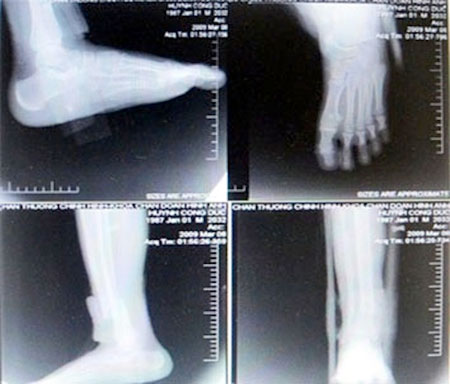

Một bệnh nhân chụp cổ bàn chân ở 4 tư thế đã bị cắt ghép phim.

Việc phát hiện “ăn phim” trên bệnh nhân rất tình cờ, khi một BS làm việc tại BV về thăm người bạn ở Bến Tre. Mẹ của người bạn bị đau vùng vai và cổ đã được người nhà đưa lên BV Chấn thương-chỉnh hình điều trị. Bác sĩ (BS) chỉ định chụp cột sống cổ ở bốn tư thế (thẳng, nghiêng, chếch 3/4 bên trái và bên phải). Bệnh nhân phải nộp 240.000 đồng để mua hai phim chụp X-quang. Tuy nhiên, sau khi xem hồ sơ, vị BS phát hiện phiếu thu tiền chụp phim X-quang cho người bệnh là loại lớn, trong khi hai tấm phim chụp thực tế thì nhỏ, nhìn không rõ. Thay vì phải chụp trên hai phim thì kỹ thuật viên đã ghép cả bốn tư thế chụp trên một phim rồi cắt làm hai, khiến tấm phim bị teo tóp phân nửa (kích thước chỉ còn 35cm x 21,5cm). Từ sự việc trên, nhiều BS của BV tìm hiểu và phát hiện hàng trăm vụ “ăn phim” đã diễn ra tại BV này kéo dài trong nhiều năm.

Theo tố cáo của các BS, khoa CĐHA, BV Chấn thương-chỉnh hình: “Các BS Hồ Văn Thạnh - Trưởng khoa CĐHA, ông Phạm Thanh Hải - Phó khoa và kỹ thuật viên trưởng Bùi Bảo Vinh có hành vi tham ô tài sản. Cụ thể, từ năm 2007 đến nay, nhóm ba người của khoa CĐHA đã chỉ đạo các nhân viên dưới quyền ghép phim, cắt phim, đổi phim, gian lận phim trong việc nhập và xuất phim cho bệnh nhân. Mỗi tháng, khoa này ăn gian của người bệnh gần 250 triệu đồng. Việc gian lận được thực hiện bằng hai cách: Đánh tráo phim X-quang (thu tiền của bệnh nhân với giá phim loại A, nhưng lại chụp bằng phim loại B rẻ hơn) và lắp ghép phim (người bệnh đóng tiền chụp cho 2 phim, nhưng khoa chụp ghép nhiều bộ phận cơ thể cần chụp trên 1 phim, rồi cắt nhỏ phim ra đưa cho bệnh nhân)”.

Chẳng hạn, bệnh nhân được chỉ định chụp cột sống cổ bốn tư thế: Thẳng, nghiêng, chếch 3/4 hai bên và BV sẽ thu tiền bệnh nhân là chụp 2 phim. Tuy nhiên, khi chụp, kỹ thuật viên thực hiện việc ghép chụp 2 hoặc 4 phần cơ thể trên một phim. Bệnh nhân hoàn toàn không biết kích thước chuẩn của phim là bao nhiêu, chỉ thấy kết quả chụp X-quang cho ra hình ảnh chụp của bốn tư thế trên cùng một phim của bệnh nhân và giao cho họ nhận 2 tờ phim đã cắt. Bệnh nhân nghĩ là đúng theo phiếu thu tiền 2 phim của BV.